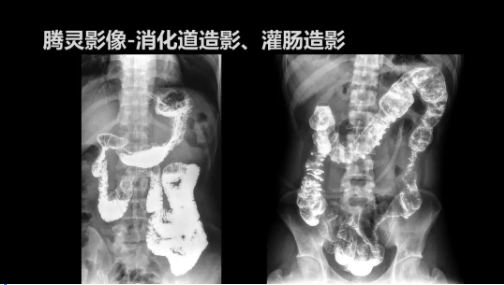

“騰靈”是安健科技的第四代動態(tài)DR產(chǎn)品,可實現(xiàn)全科室應(yīng)用。如各類常規(guī)的X線檢查、消化道檢查、骨科檢查、婦科、兒科檢查等。此外,安健科技為“騰靈”在真正意義上實現(xiàn)多科室、多功能診斷進行了多項針對性設(shè)計。

此外,“騰靈”為了能夠幫助醫(yī)生更快速、有效的定位病灶,還增加了多項精準(zhǔn)診斷保障功能,如支持動態(tài)觀察診斷,實時高清點片等?!膀v靈”透視切換高清點片曝光,捕捉關(guān)鍵病灶診斷僅需0.8s,同時還支持圖像局部放大,醫(yī)生可自由切換15’12’和9’三種放大模式,另外,“騰靈”還支持視頻保存、回放功能,幫助醫(yī)生在檢查結(jié)束后通過回放查看細節(jié),為醫(yī)生的診斷增加信心。